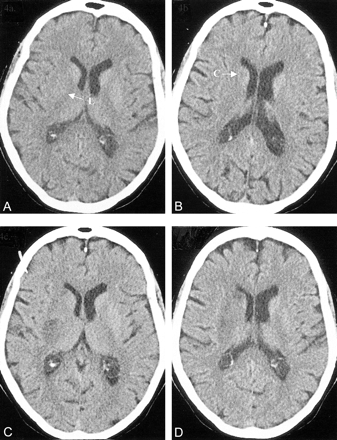

CT scans in a 65-year-old woman with left-sided hemiplegia, hemianopia, and neglect less than 3 hours after symptom onset.

A and B, Baseline CT scans show hypoattenuation with swelling and effacement in regions M1, M2, insula (I), M4, and M5 (ASPECTS = 5). Intravenous thrombolysis was administered.

C and D, Follow-up CT scans show a large area of hypoattenuation involving much of the MCA territory. The patient was dependent at 3 months.